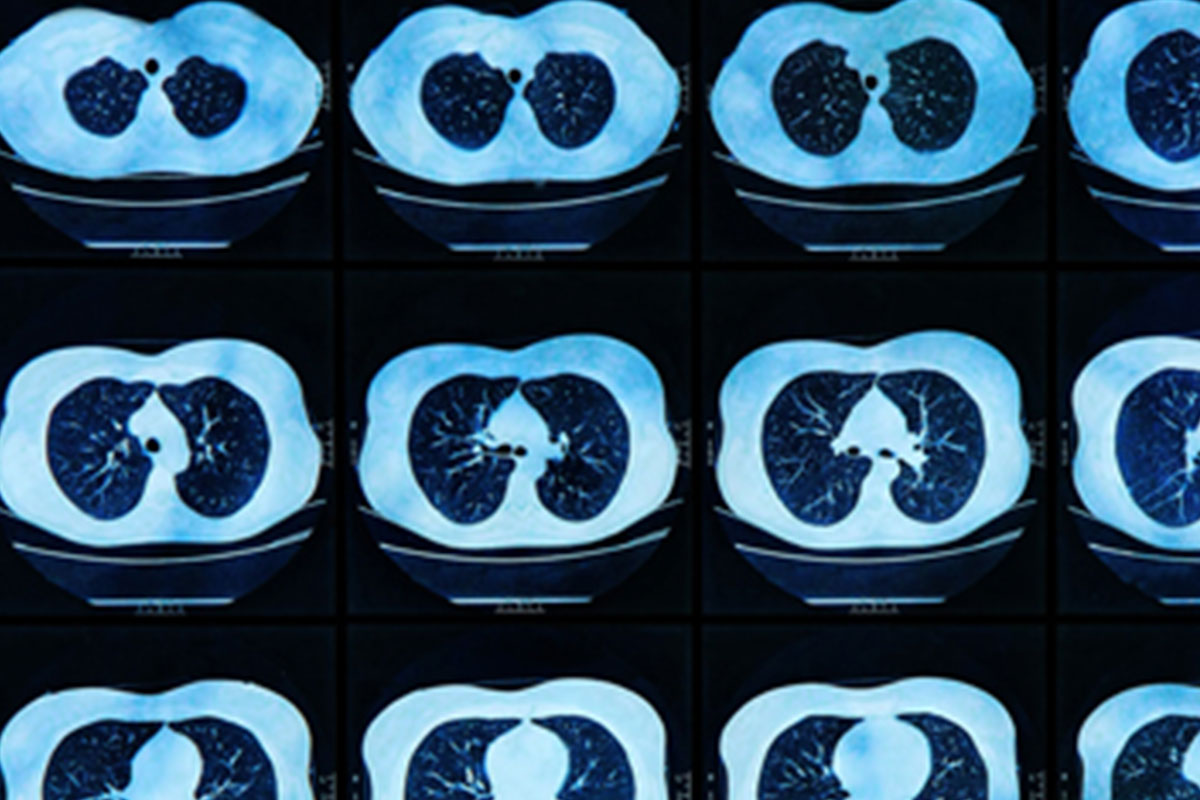

Computed Tomography (CT)

CT Low Dose Lung Cancer Screening